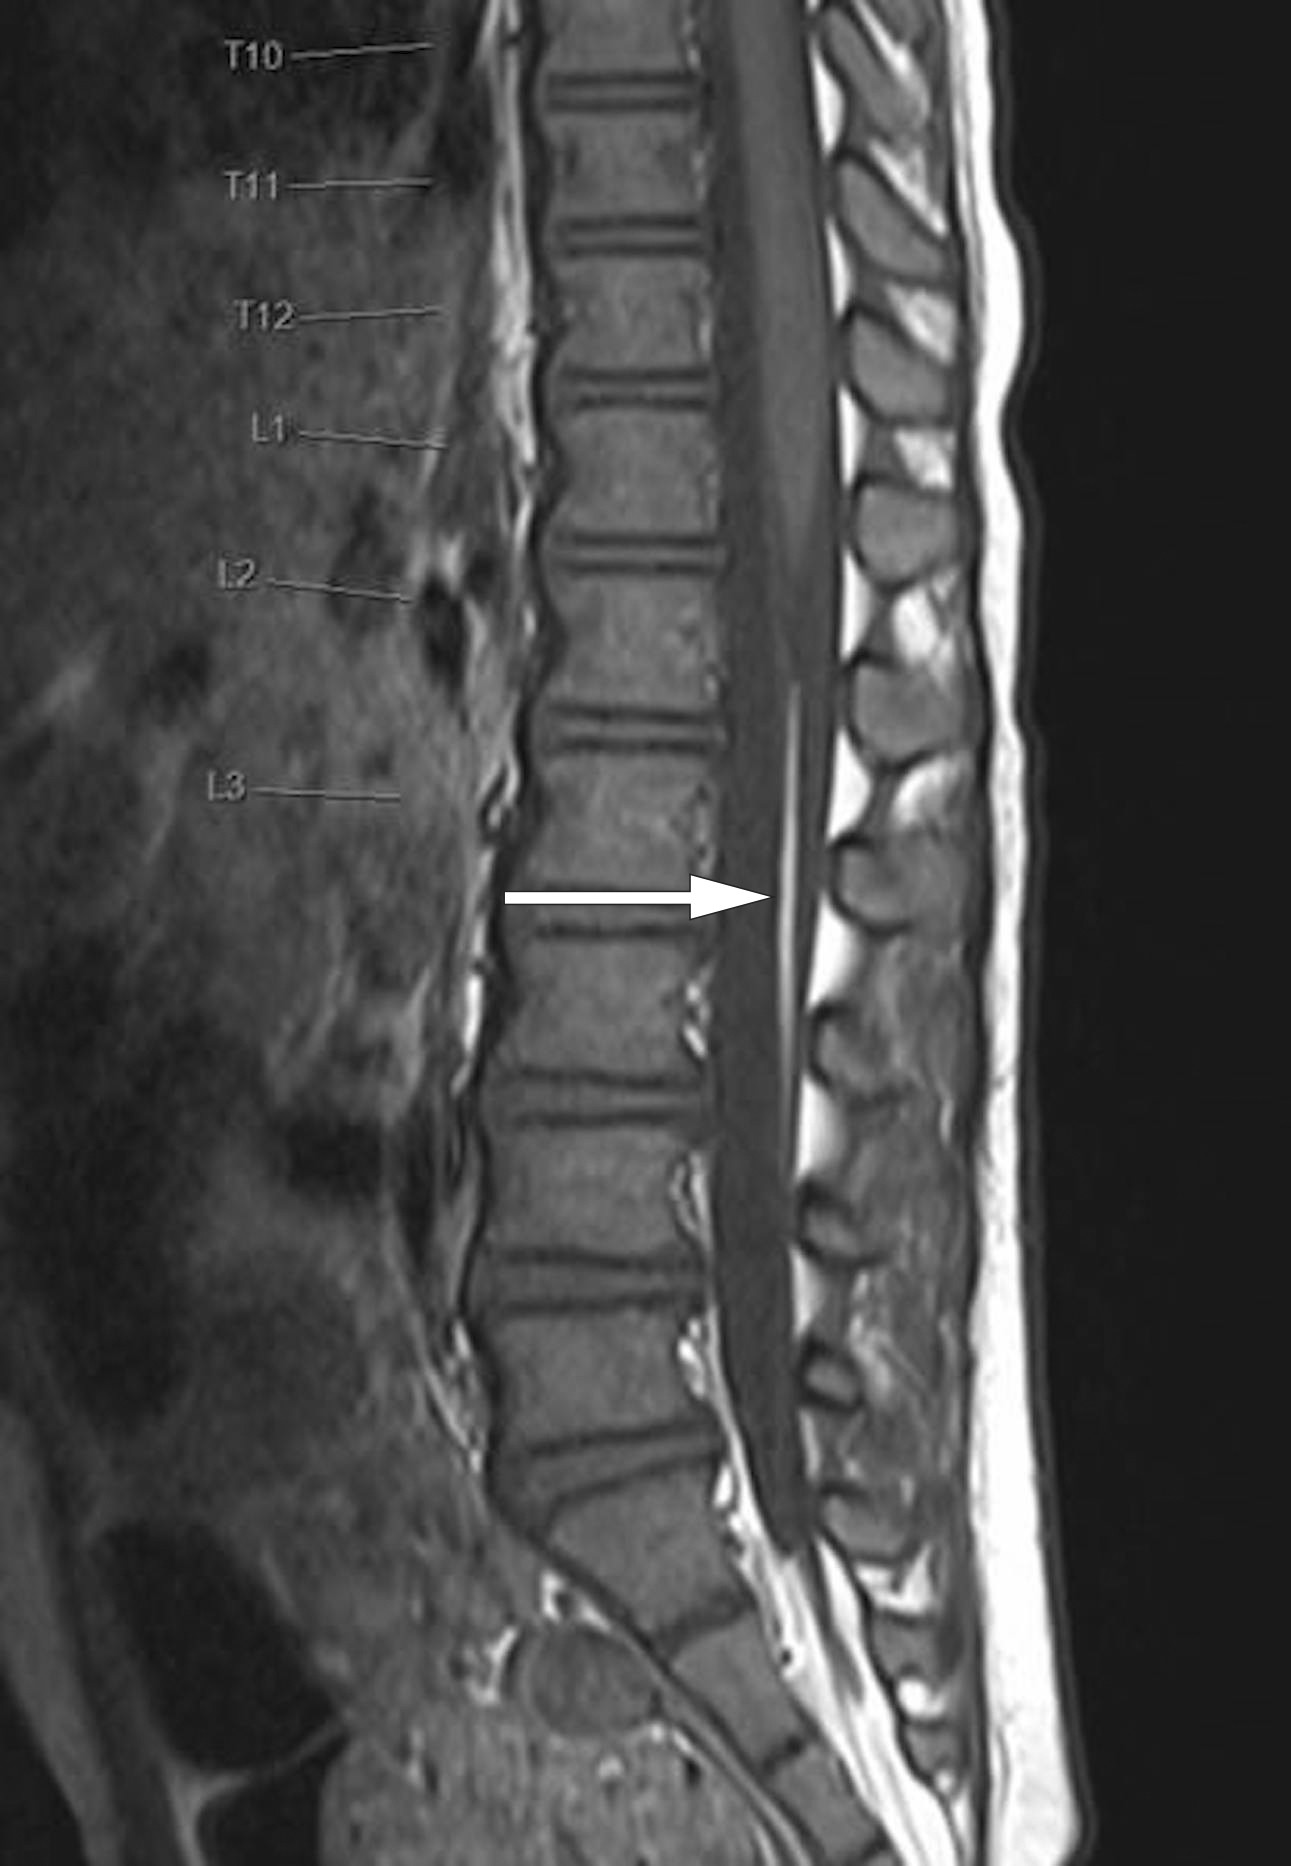

Pasienter med tilfeldig påvist Chiari-malformasjon type 1 og få eller ingen symptomer bør ikke opereres, selv med påvist syringomyeli (figur 4). Syringomyeli kan likevel gi grunn til en mer aktiv tilnærming hos barn, særlig ved vesentlig progrediering ved etterfølgende MR-kontroller. Tilstanden bør også behandles hos barn med skoliose og samtidig syringomyeli.

Hos ca. 50 % av pasientene påvises syringomyeli, en cystisk utvidelse av ryggmargens sentralkanal (figur 3). Omfanget kan variere fra et lite segment av ryggmargen til en langstrakt (holocord) syringomyeli. Det finnes forskjellige teorier om hvordan syringomyeli ved Chiari-malformasjon type 1 oppstår. Likevel er ennå ikke alle aspekter av denne problemstillingen godt forklart (12).

Andre assosierte funn kan være skjelettanomalier i kraniocervikalovergangen, skoliose eller intraspinale lipomer.